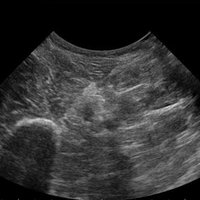

Das MyLab™One steht für das revolutionäre „Arm-held“ Hochleistungs-Ultraschallsystem mit 12”-Full-Touchscreen. Aufgrund seines geringen Gewichts und der Tragbarkeit kann es auch ohne Arbeitsfläche verwendet werden. Eine einzelne Person kann dieses Gerät aufgrund seiner einzigartigen Funktionen allein und selbstständig bedienen.

Das Ultraschallsystem MyLab™One zeigt exemplarisch den modernen Bedarf an Diagnosekapazitäten in verschiedenen Anwendungsbereichen: Radiologie, Kardiologie, Phlebologie, Frauenheilkunde, Orthopädie, Regionalanästhesie, Sportmedizin, Interventionell, Rheumatologie, Erste Hilfe, Notfallmedizin, Vaskuläre Reihenuntersuchungen, Allgemeinpraxis.

Kompromisslos für den Point-of-Care: konzipiert für Ihre Umgebung

Die kompromisslose Ausrichtung auf den Point-of-Care bedeutet Fokus und Achtung auf spezifische Anwendungen, um bestimmte technologische Entwicklungen zu nutzen, die die wirksamsten Lösungen bewirken. Das MyLab™One kombiniert leistungsstarke Software mit einer Bedieneroberfläche, die speziell auf die Anwendung abgestimmt ist, und einem umfassenden Zubehör, das das MyLab™One zu einem perfekten System für alle klinischen Umgebungen und Workflows macht.